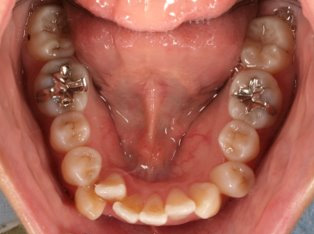

乱ぐい歯、でこぼこがとても酷い状態になります。歯が前後的に重なってしまっている、八重歯になっているなどがこのジャンルに入ります。

顎の大きさと歯の大きさのギャップが大きく、時には歯を抜かないと矯正治療ができない場合もあります。当院では治療期間が長くなるが抜かない治療方針など、一つの治療プランだけでなく、さまざまな可能性の治療方針を説明させて頂くよう心掛けております。こういった考え方はインフォームド・チョイスと言われ近年大切にされている考え方と言われております。

治療前

治療終了前